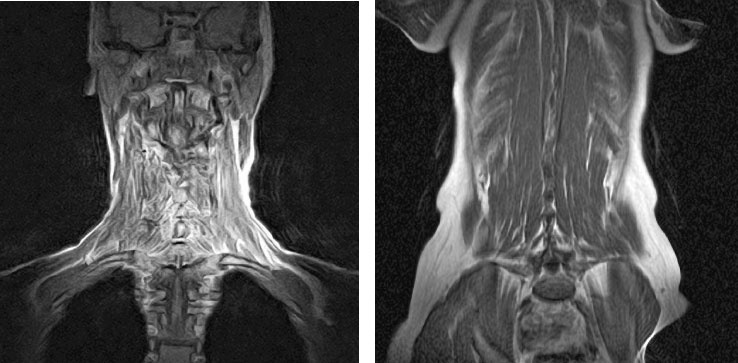

Рисунок 18. Фронтальный вид мышц головы (слева) и поясницы (справа), полученный путем МРТ. Мышцы головы крепятся преимущественно к лопаткам, ключицам и грудине. Использование рук для поднятия и удержания веса подвергает затылочные позвонки стимулирующей компрессии. То же касается мышц, связывающих между собой тела и поперечные отростки поясничных позвонков.